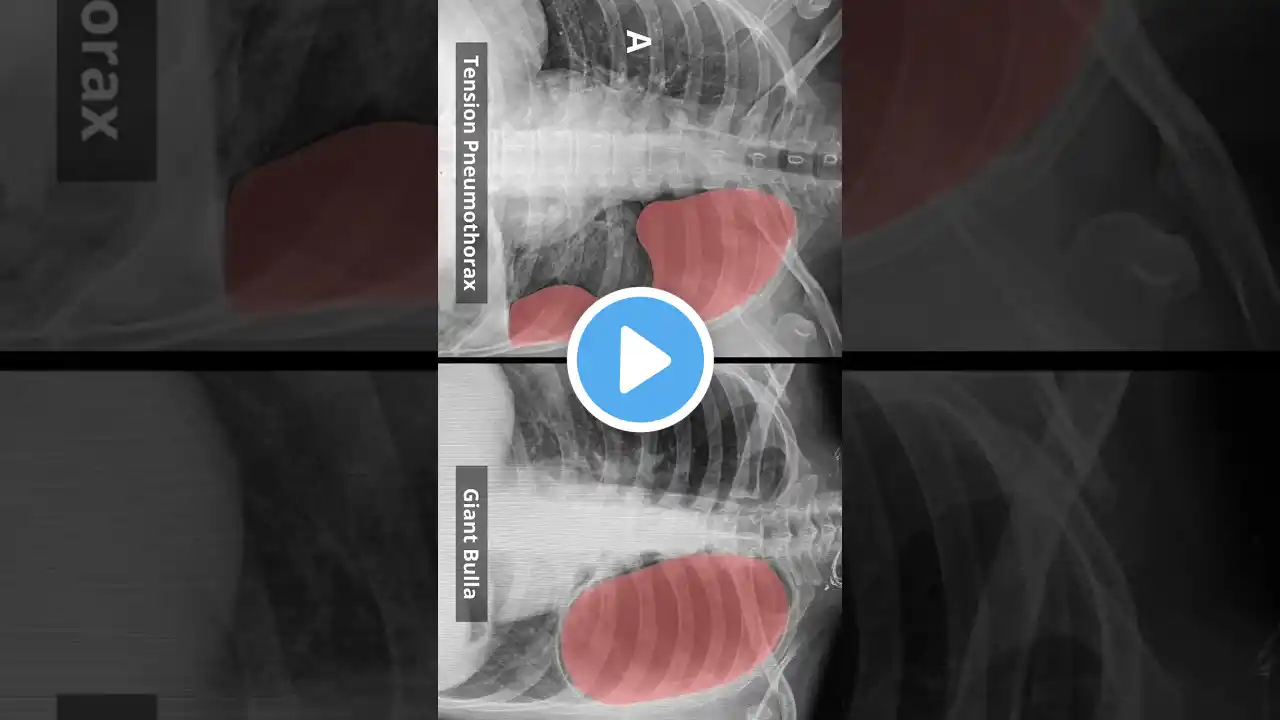

Kia ora team, Let's talk about the difference between a haemothorax, a pneumothorax and a tension pneumothorax and how they can be life-threatening. Haemothorax is the accumulation of blood in the pleural space. Significant blood loss into the pleural space can collapse the lung and cause hypoxia, and lead to hypovolemic shock, decreasing blood pressure and reducing perfusion to vital organs. Pneumothorax is the presence of air in the pleural space. Tension pneumothorax is a type of pneumothorax where air enters the pleural space and cannot escape, creating increasing pressure. A tear in the lung or chest wall creates a one-way valve that allows air to enter the pleural space but not escape, causing pressure to build up with each breath. The trapped air increases pressure within the chest cavity. The increasing pressure pushes the mediastinum (heart, trachea, and major blood vessels) toward the opposite side of the chest ( Mediastinal Shift ). The affected lung collapses, and the increased pressure can also compress the opposite lung and cause hypoxia. Compression of the heart and major blood vessels reduces venous return (decreased preload) and cardiac output. This can cause Obstructive shock. Happy studying team